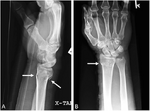

Chauffeur's fracture[4] Chauffeurs intra-articular fracture of radial styloid forced ulnar deviation of the wrist causing avulsion of the radial styloid Chauffeur's fracture Archived 2020-09-18 at the Wayback Machine at Wheeless' Textbook of Orthopaedics online Chauffeur-Fraktur und PSU bei Ulnavorschub mit Impaktation 83W - CR ap - 001.jpg

Colles' fracture Abraham Colles distal radius fracture with dorsal angulation, impaction and radial drift fall on outstretched hand Colles' fracture at Who Named It? Colles fracture1.png